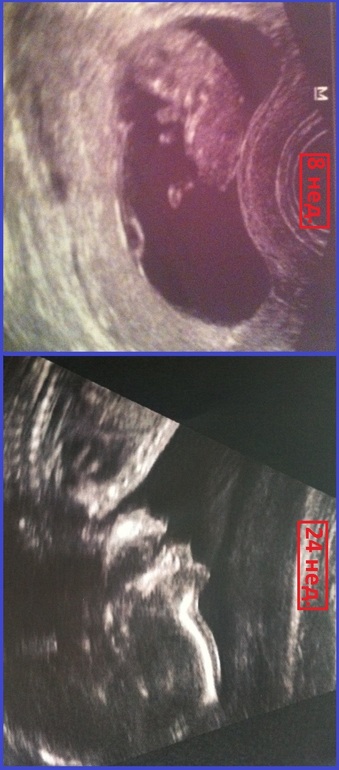

Классный пост! Спасибо! Столько позитива! Легко вам доносить и родить в срок. Удивило, что на 7 неделе может быть уже такое пузо и что на 8 неделе на узи там уже такой прям человек! Супер!

Мне кажется, что пузо у меня с самой стимуляции...А вообще..Намучили меня за три года:)

Результаты узи 14 недель! УЗИ на 20-й неделе- хотела похвастаться, а получаются только вопросы